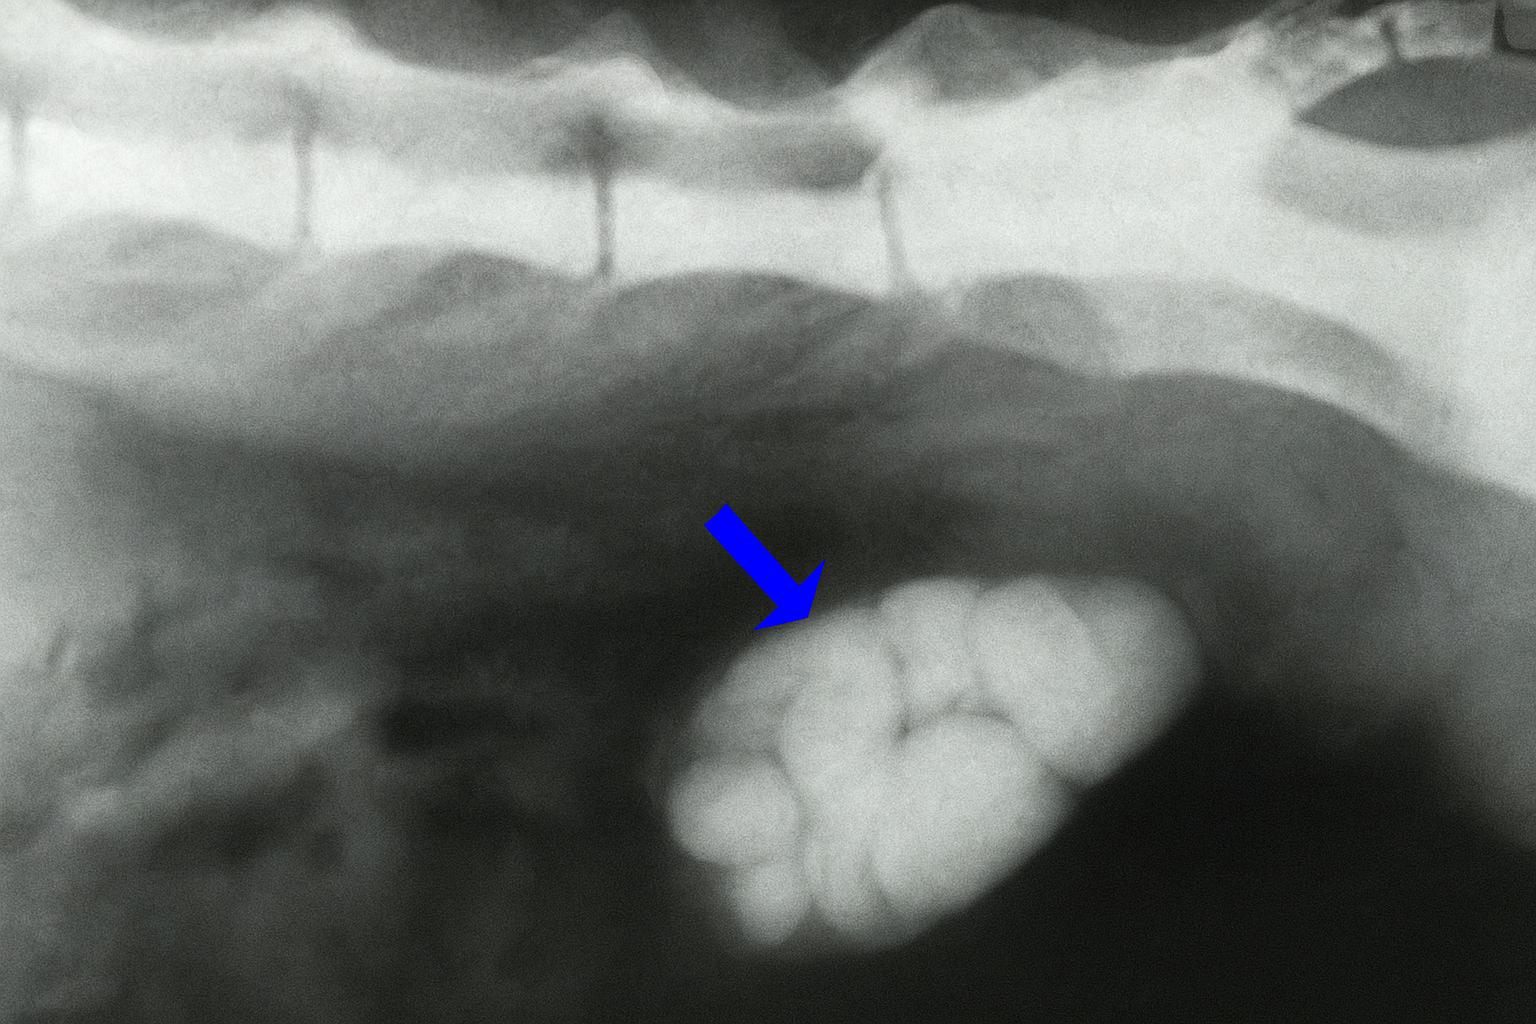

3. Obstrucción uretral

La causa más evidente de que un gato vaya al arenero y no consiga orinar es la obstrucción uretral, que ocurre cuando algo tapa la uretra e impide el paso de la orina. Esto provoca su acumulación en el organismo del gato y puede tener consecuencias fatales para el felino. La principal causa de obstrucción son los tapones uretrales, seguidos de la urolitiasis o cálculos:

- Tapones uretrales: son acumulaciones de sangre, tejido muerto, mucoproteínas o células inflamatorias mezcladas con material cristalizado, generalmente estruvita. Suelen formarse por inflamación persistente de la uretra o de la vejiga, en ocasiones asociada a la CIF.

- Cálculos: son sedimentos en las vías urinarias que aparecen cuando se supera el umbral de ciertos minerales en la orina, siendo los más frecuentes los de estruvita o de oxalato cálcico.